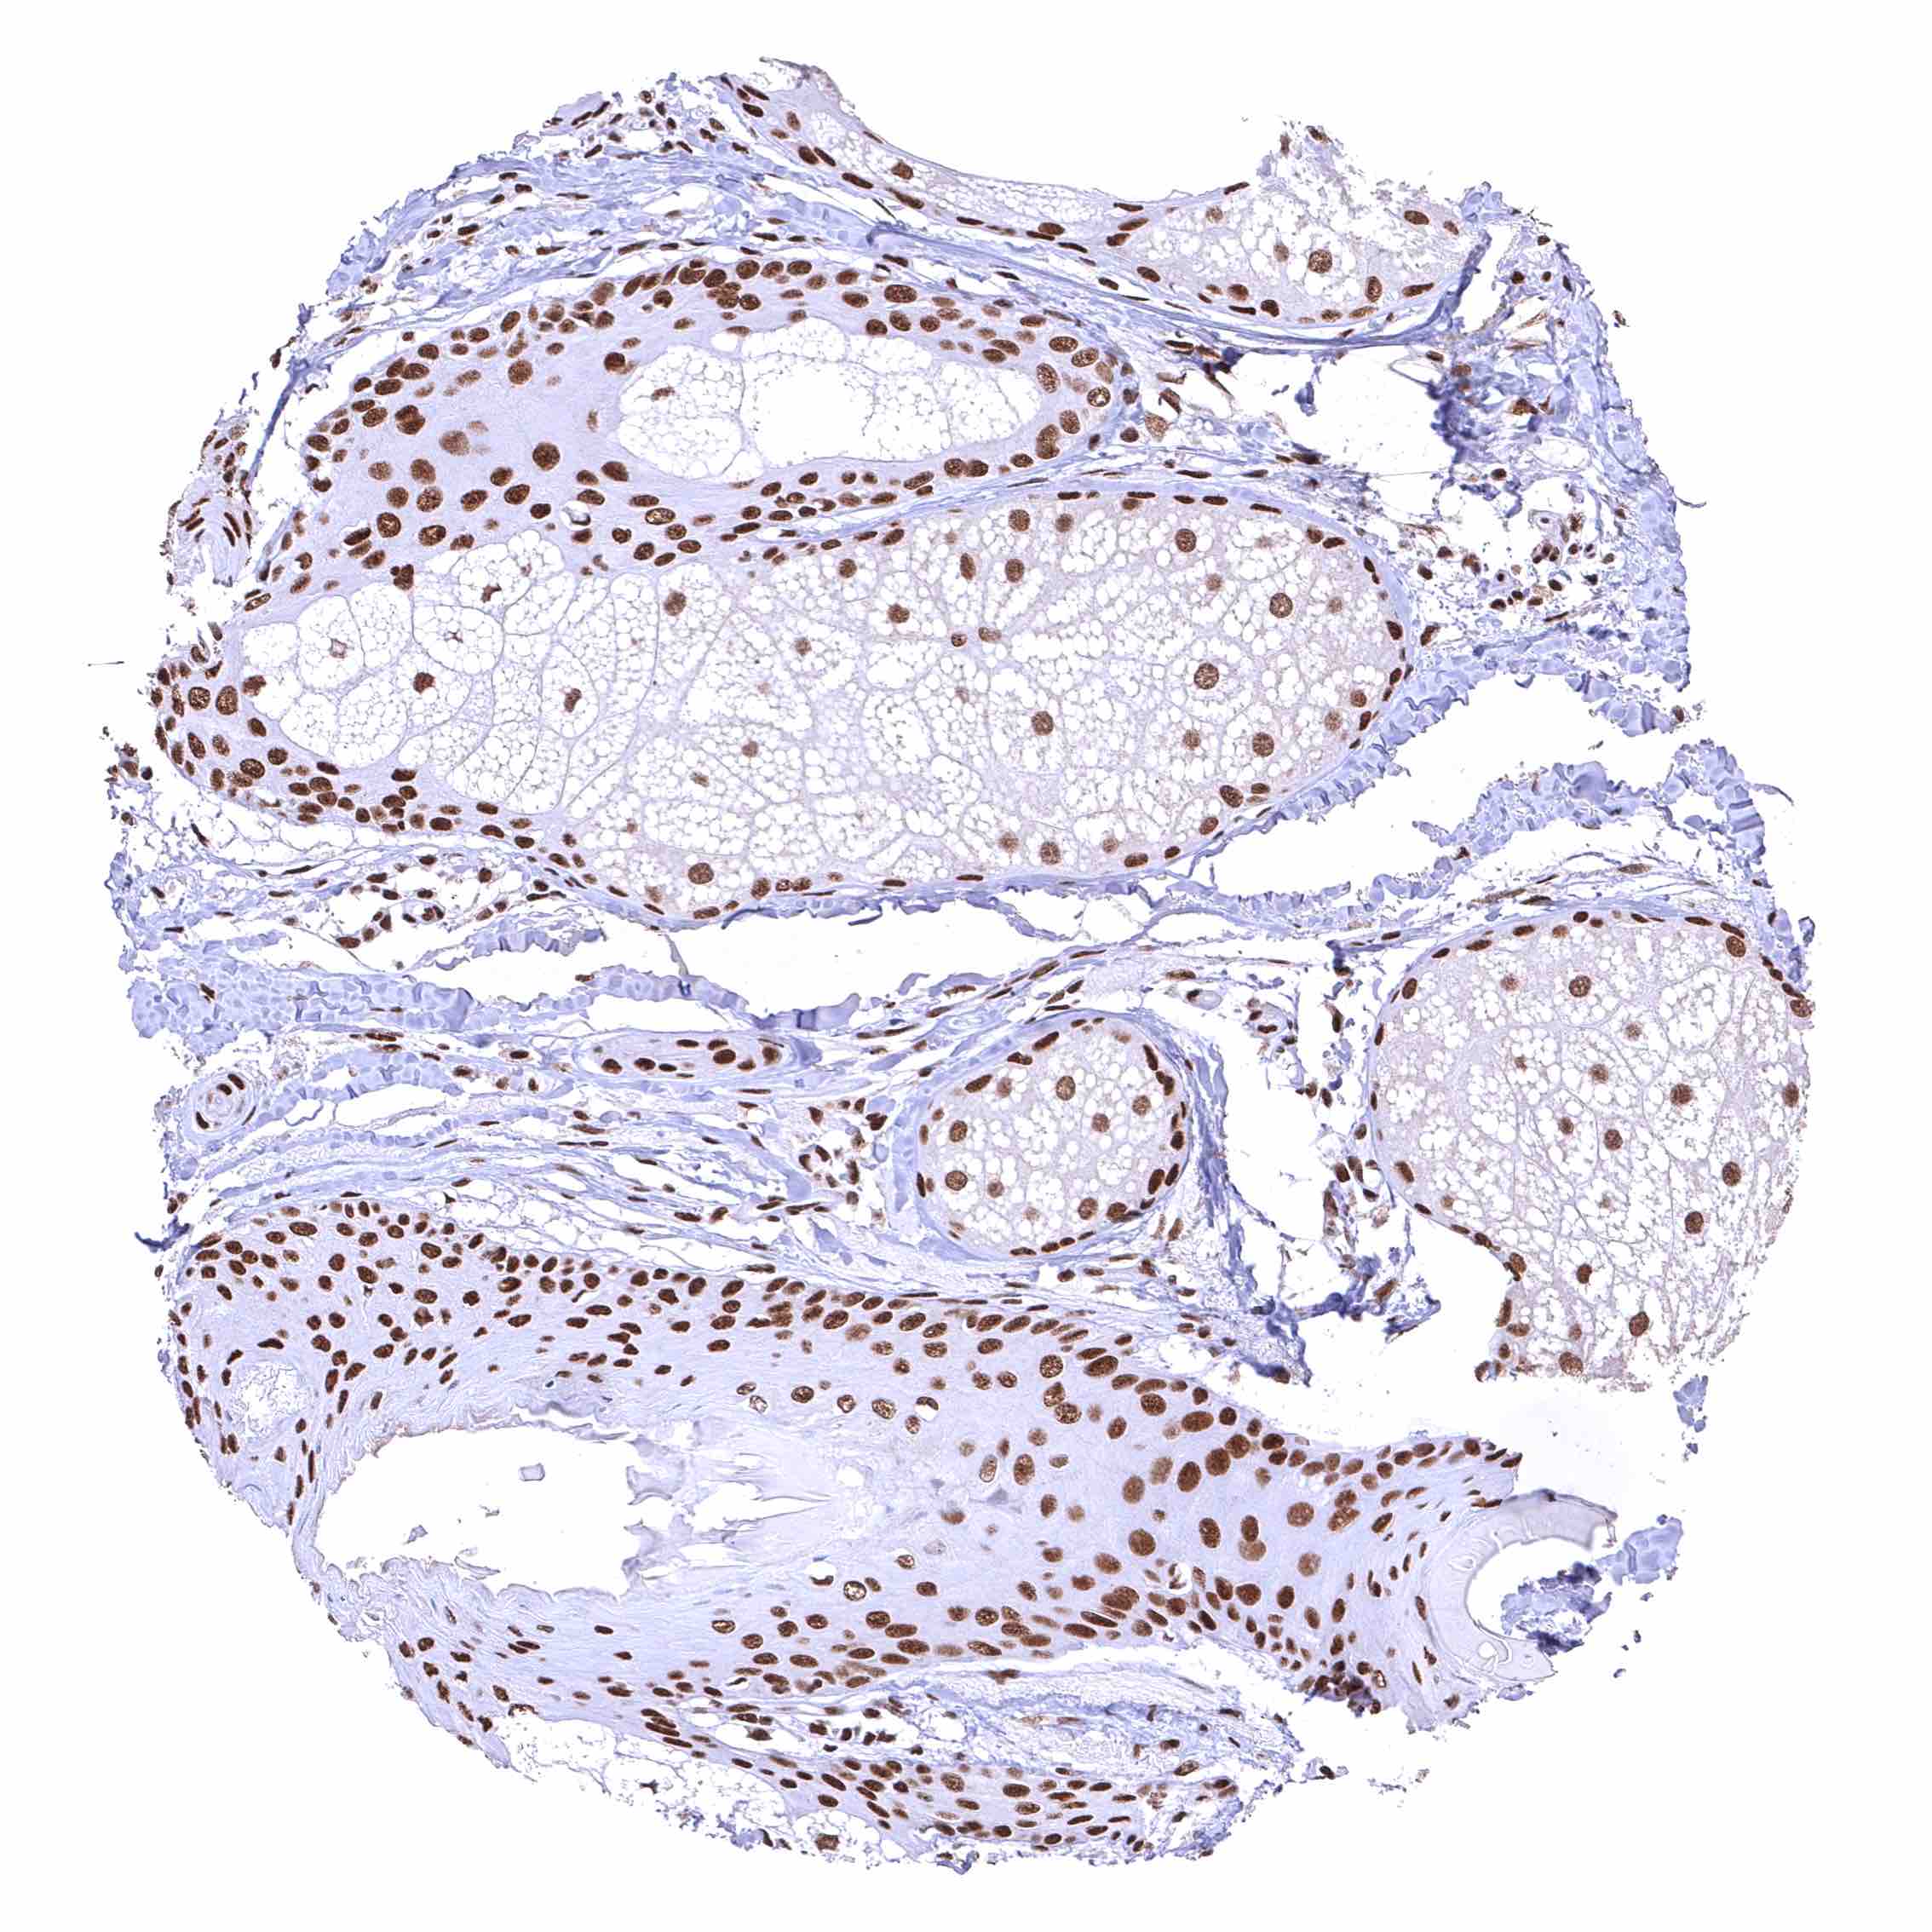

BRD4 antibody [HMV4275] HistoMAX™

Esophagus, squamous epithelium – Distinct nuclear BRD4 staining of squamous epithelial cells with a slight decrease of the staining intensity towards the most superficial cell layers.